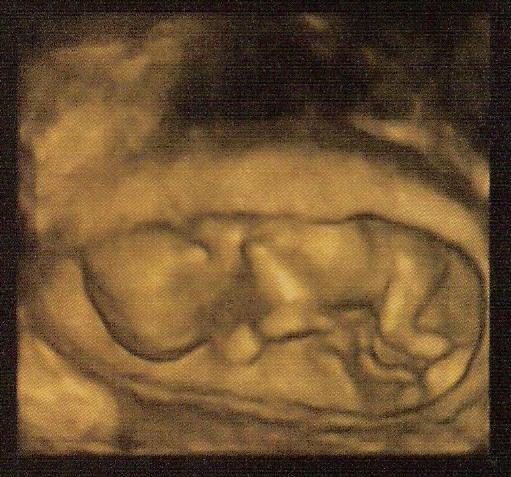

Fantasztikus élémény volt! :) Minden rendben van a babival! :) Doki át is kapcsolata a az UH- gépet 4D-re, ahol nagyon jól látszott a kicsike!

Éppen szundikált, és el volt fordulva, fel kellett ébreszteni, hogy forduljon meg (sokat kellett köhögnöm, meg az UH. fejjel is rezegtették kicsit a hasamat, de vagy 5-6 perc volt mire felébredt

és megforuldt, hogy a nyakirendőt is meg tudja mérni az orvos).

Babi Adatai:

BPD (Fej átmérője): 19 mm

NT (Nyaki redő): 1, 3 mm

Fej körfogata: 72 mm

Has körfogata: 57 mm

Comcsont hossza: 5 mm

CRL (ülőmagasság): 61 mm

Magazti súly: 54 g

Orrcsont: látható

Számított terhességi korom: 12 hét 4 nap

Pici szívverését is hallottuk! Nagyon édes volt és megható az egész vizsgálat, mikor kijöttünk a vizsgálóból eleredtek a könnyeim már kint alig bírtam!

Kaptunk is DVD-t a vizsgálatról, így a nagyszülők is meg tudták nézni! :)

Maj teszek fel képet is, csak be kell szkennelni a felvételt! :)